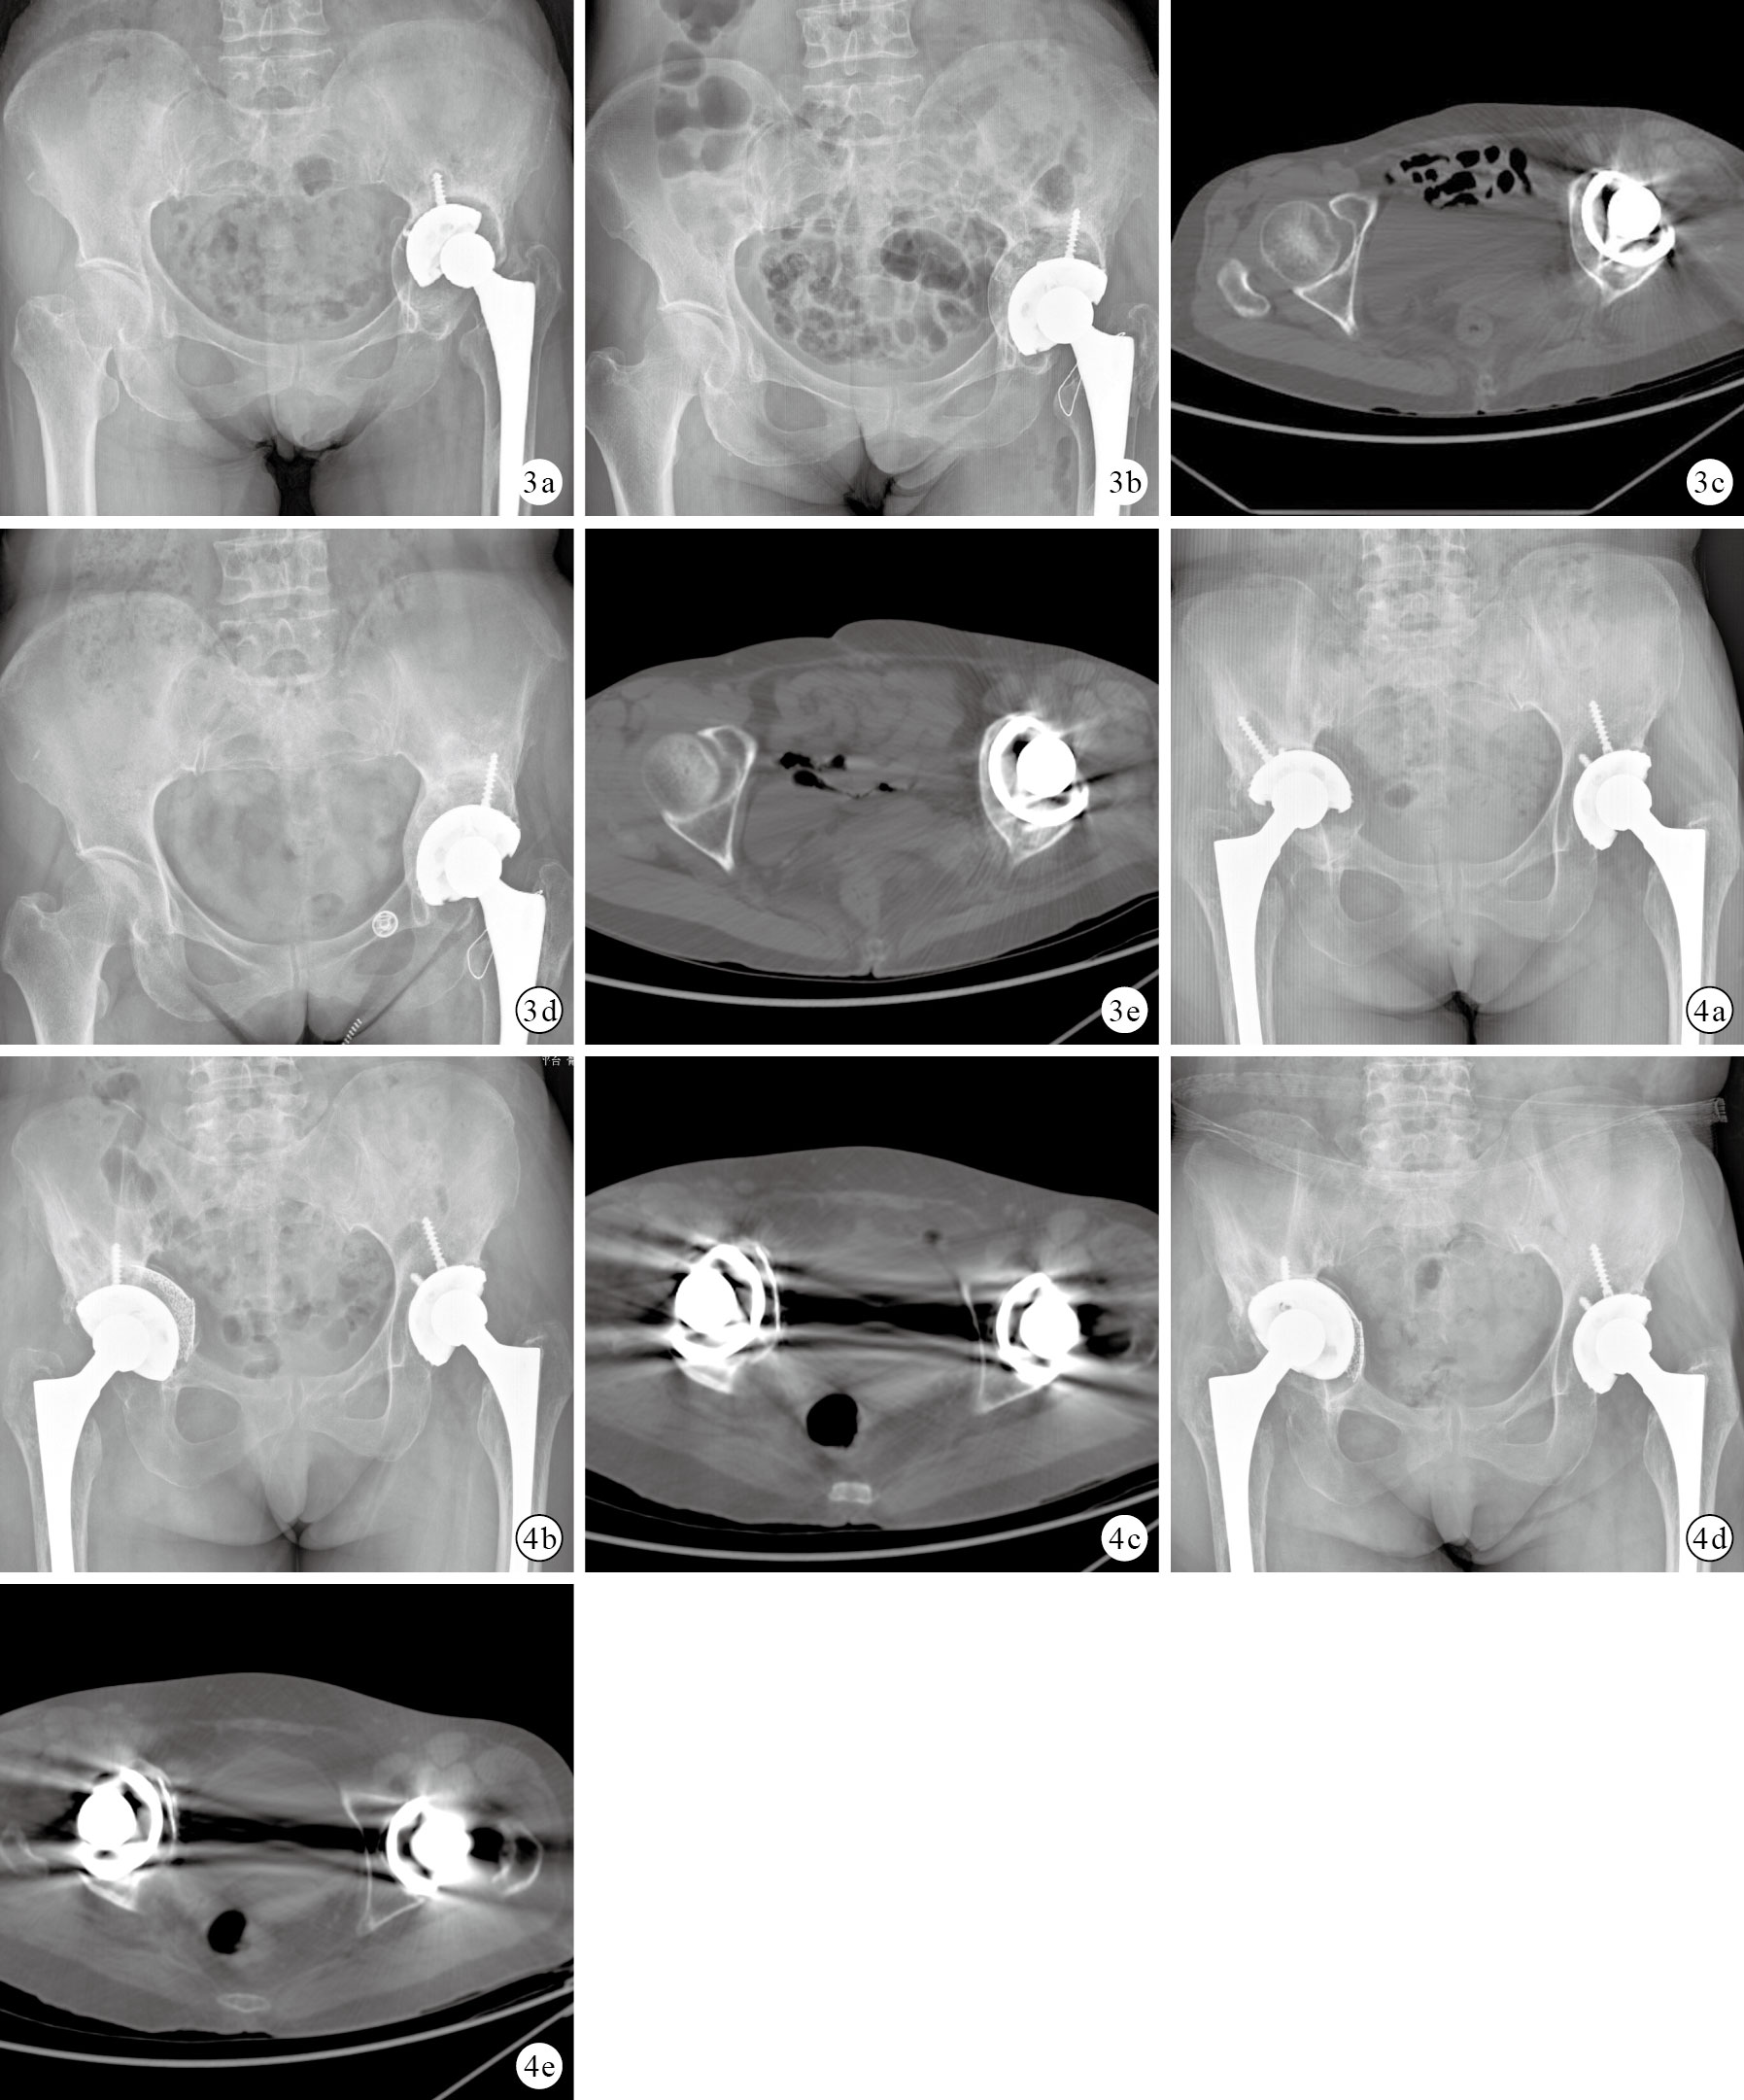

術后患者均獲隨訪,隨訪時間7~25個月;其中A組8~23個月,平均12.6個月;B組9~21個月,平均11.8個月;C組7~18個月,平均11.3個月;D組7~25個月,平均12.1個月。A組2例術后發生髖臼假體松動,行翻修術。B組1例術后發生坐骨神經損傷,口服甲鈷胺治療,隨訪6個月后明顯好轉;1 例髖關節脫位,經手法復位石膏外固定、牽引治療后無復發。其余患者無相關并發癥發生。見圖 1~4。